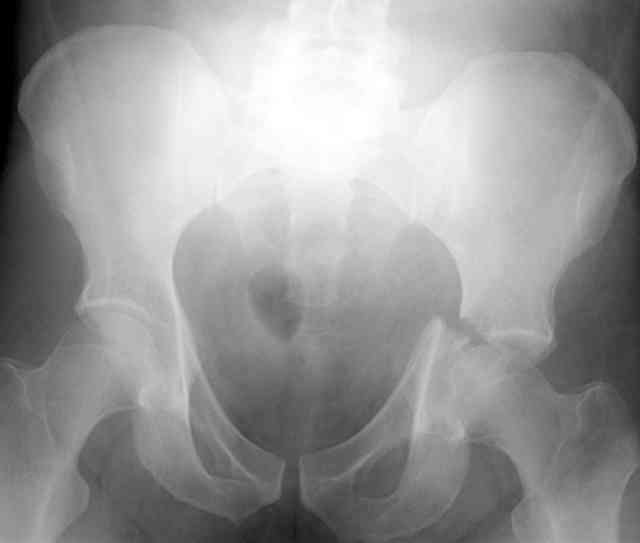

Stabilize anterior column with fluoroscopically guided screw across this end of the transverse fx - As usual, after your reduction of the femoral head, the transverse fx became minimally displaced - slightly gapped without stepoff. I usually (reduce &) stabilize the medial side of the posterior column (transverse fx) with a short plate - before placing the anterior screw unless the transverse fx is undisplaced.

Biggest problem appears to be impaction & comminution of the posterior wall fx site - you've left out some CT cuts. This is not just fragments in joint. It may leave a deficient area, &/or block satisfactory posterior wall reduction.

May need to bone graft elevated articular fragments. Lag screws & more lateral contoured plate to buttress PW. Make sure this reduction is

anatomical.